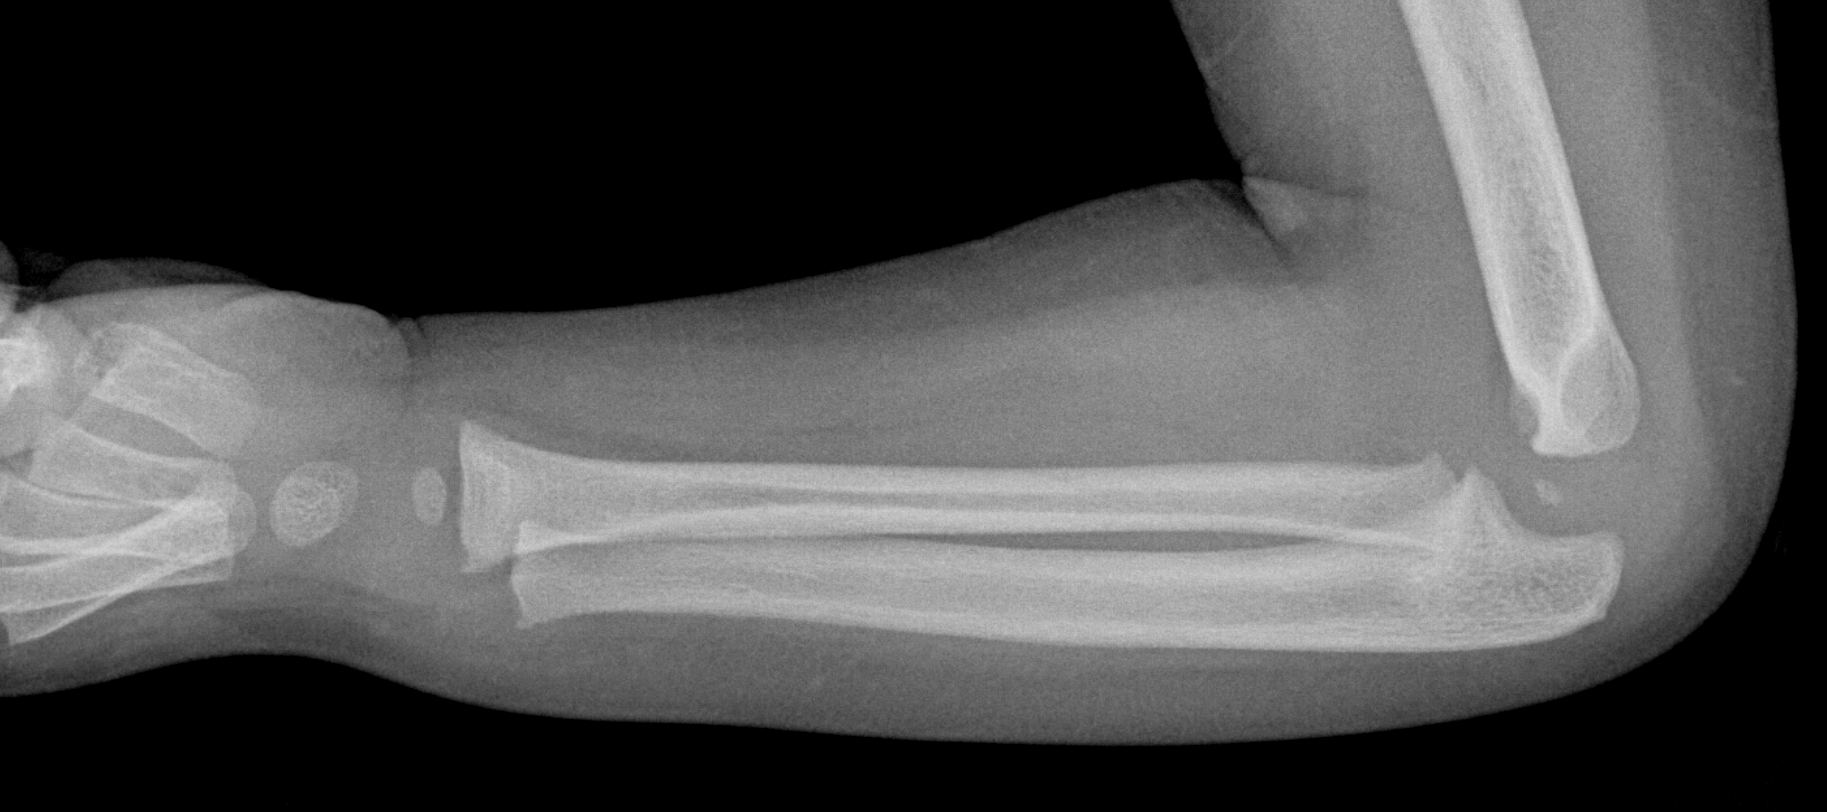

Info Images Findings Impression Reco/Acuity Case Images View Images / Launch Visage Case Notes History 2-month-old presents with decreased right arm movement, increased fussiness, and increased sleepiness for 2 days. Suspected non-accidental trauma. Exam Skeletal survey Prior Study none Dicom View Reference Material

Section 1 Submit Findings CB1550 Findings Skeletal Survey - Technique Check Skull AP/Lat Yes No Cervical and Thoracolumbar spine Yes No Chest X-Ray Yes No Ribs – Left/Right Oblique Yes No Abdominal X-Ray Yes No Pelvis with both hips Yes No Bilateral Humerus, Forearm, Hand Yes No Bilateral Femur, Tibia/fibula, feet Yes No Any additional lateral views of the extremities Yes No The exam is over or under penetrated. Yes No The exam may or may not be limited by overlying structures or soft tissues, body habitus, patient positioning, support devices, or motion. Yes No The area of concern is indicated by the patient, technologist, or care provider. Yes No The area of concern is included on the exam. Yes No Soft Tissues There is soft tissue swelling, indistinctness of fat/muscle planes, gas, or laceration in the area of clinical concern. Yes No There is an effusion, fat pad displacement, or fat fluid level. Yes No There is a radiodense or lucent foreign body. Yes No There are other densities, calcifications, post-surgical changes, or support devices in the soft tissues. Yes No Any support lines/tubes. Yes No Bone There is a break or interruption of the continuity of the cortical or cancellous bone. Yes No There is overriding of the trabeculae with apparent sclerosis. Yes No There is displacement of a fracture fragment. Yes No There is bowing of the bone in addition to the fracture at the apex of the bowed bone concerning for the greenstick. Yes No There is a spiral fracture of the leg concerning for toddler’s fracture. Yes No There is abnormal angulation or bulging of the cortical surface relative to the normal cortex which could be from a buckle or torus fracture. Yes No There is a displaced fragment which may be from avulsion by a tendon, ligament, or joint capsule or from a comminuted or other fracture. Yes No The stress trabeculae or other trabeculae of the cancellous bone are interrupted or otherwise abnormal. Yes No There is subperiosteal or endosteal reaction which could indicate a healing or subacute fracture or other abnormality. Yes No There is hard/soft callus formation. Yes No There is remodeling of the bone. Yes No There is a corner fracture or metaphyseal lesion that could be from nonaccidental trauma. Yes No There are multiple fractures of different ages. Yes No There are vertebral body/spinous process fractures. Yes No There are rib fractures. Location - posterior or lateral. Yes No There is scapular/sternal fracture. Yes No There are fractures of the digits. Yes No There are wormian bones. Yes No There are intrasutural bones. Yes No There is metaphyseal abnormality (lucencies, increased density, erosion) which may be from something other than injury such as stress, metabolic disease (e.g. rickets with loss or distortion of the zone of the provisional calcification), neoplasm (e.g. leukemia), heavy metals, inflammation, or infection. Yes No There are metaphyseal spurs. Yes No There are bony deformities involving multiple bones. Yes No The bones are gracile. Yes No There are non-healing fractures. Yes No There is/are focal or multifocal lytic/lucent, blastic/sclerotic or mixed density lesion(s) or other abnormality. Yes No Overall bone density is increased or decreased with or without thinning or thickening of the cortical or cancellous bone. Yes No Growth plates, ossification centers, apophyses The growth plate(s) is/are abnormal. Yes No There is widening of the physis from a fracture with or without displacement of the epiphysis (Salter-Harris I). Yes No There is a fracture through the physis which then extends into the metaphysis with or without angulation or displacement (S-H II). Yes No There is a fracture through the physis which then extends into the epiphysis and is intra-articular, with or without angulation or displacement (S-H III). Yes No There is a fracture through the metaphysis, physis, and epiphysis which extends into the joint space with or without angulation or displacement (S-H IV). Yes No There is narrowing of the physis from a compression fracture (S-H V). Yes No The apophysis, epicondyle, secondary ossification center, or accessory ossicle is displaced or otherwise abnormal. Yes No The ossification centers are underdeveloped. Yes No Joints and alignment There is an effusion, fat pad displacement, or fat fluid level. Yes No The epiphysis or subchondral bone is fractured, interrupted, flattened, compressed, impacted, displaced, or otherwise abnormal. Yes No There is an intra-articular loose body or chondrocalcinosis. Yes No The joint is widened, narrowed, dislocated, malaligned, or incongruent. Yes No There is pseudoarthrosis. Yes No Other findings There are developmental changes or other anatomic variants or other existing conditions that may or may not be contributing to symptoms which can or should be further evaluated non-emergently or are otherwise incidental. Yes No The remainder of the exam is abnormal for age. Yes No The lungs show focal airspace opacity. Yes No There is pneumothorax. Yes No There is organomegaly. Yes No There is intra-abdominal calcification. Yes No There is displacement of the bowel loops. Yes No There is free intraperitoneal air. Yes No The bowel loops are dilated/obstructed. Yes No There is paraspinal soft tissue abnormality. Yes No